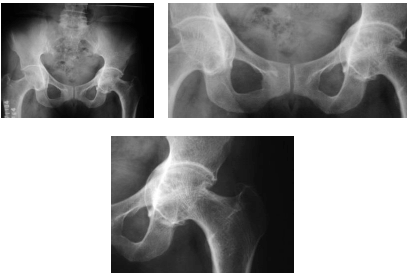

Paciente com 50 anos de idade, do sexo feminino, apresenta dor articular crônica em ambos os quadris, sem trauma ou febre e sem outras queixas ou outras patologias conhecidas. Radiografias convencionais da bacia por ela realizadas apresentaram as seguintes imagens.

Há evidência de erosão e(ou) cistos subcorticais secundários à artropatia degenerativa da articulação coxofemoral esquerda.

Os achados são típicos de protrusão acetabular (protrusio acetabuli), um achado que pode resultar em síndrome do impacto femoroacetabular.